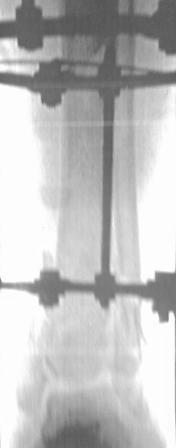

Больной 41г переведен из ЦРБ, травма в результате ДТП- 5 дней назад, произведена ПХО раны, наложена гипсовая повязка.

Об-но; начиная с с/з голени продольно - почти циркулярная рана, с признаками инфицирования - покраснение, отечность, усиление боли, местная т-ра и мутные кровянистые выделения из раны, и выраженная деформация голени. В отд нашей коллегой в экстренном порядке в задней поверхности голени щвы распушены, выпушено около 50мл мутной гематомы, АВФ, умеренная дистракция, антибиотики, и т.д.

2.Не могу, потому что аппарат Илизарова наложен нашей молодой коллегой в экстренном порядке, и несовсем удачно и с ошибками, но главную функцию для данного случая -дистракцию выполняет,( поэтому я писал, что будем делать перемонтаж.)

2. Не могли бы Вы дополнить иллюстрационный материал фотографиями конечности, включающей колено, голень и стопу, а также рентген снимки, хотя бы показывающие полностью компоновку аппарата.